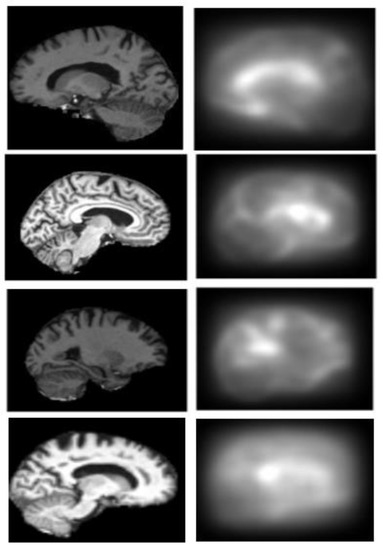

2.3. Generation of Saliency Maps

2.3.2. Bottom-Up Saliency Maps (

2.3.3. Final Saliency Map